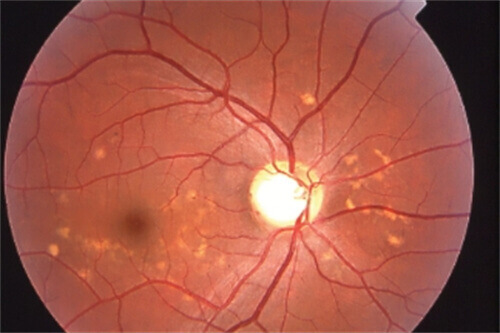

实例一:65岁男性患者,因"右眼视力突然下降伴视物变形"就诊。经检查确诊为右眼黄斑裂孔,视力仅0.1。雷医生为其进行了小创口玻璃体切割联合内界膜剥除手术,术后3个月复查,黄斑裂孔闭合,视力修复至0.6。

实例二:42岁女性糖尿病患者,因"双眼视力逐渐下降"就诊。检查发现双眼严峻的糖尿病视网膜病变伴黄斑水肿。雷医生为其制定了系统的治疗方案,包括视网膜激光治疗和抗VEGF药物玻璃体腔注射。经过6个月治疗,患者视力稳定,黄斑水肿明显减轻。

实例三:28岁男性,因"右眼外伤后视力丧失"急诊入院。检查发现右眼复杂性视网膜脱离伴玻璃体积血。雷医生急诊为其进行了玻璃体切割联合视网膜复位手术,术后3个月复查,视网膜复位良好,视力修复至0.4。

根据临床统计,雷医生主刀的视网膜脱离手术成功概率超过90%,黄斑手术视力改善率超过80%。

对于糖尿病视网膜病变患者,通过系统治疗可使90%以上患者避免失明。

医院眼底病专科设备可靠,拥有国内外很棒的眼科检查及手术设备,包括光学相干断层扫描仪(OCT)、眼底荧光造影仪、视觉电生理检查仪、超声生物显微镜(UBM)等。

中心开展各种黄斑疾病的诊断和治疗,包括老年性黄斑变性、黄斑水肿、黄斑裂孔、黄斑前膜等,年手术量超过1000例。